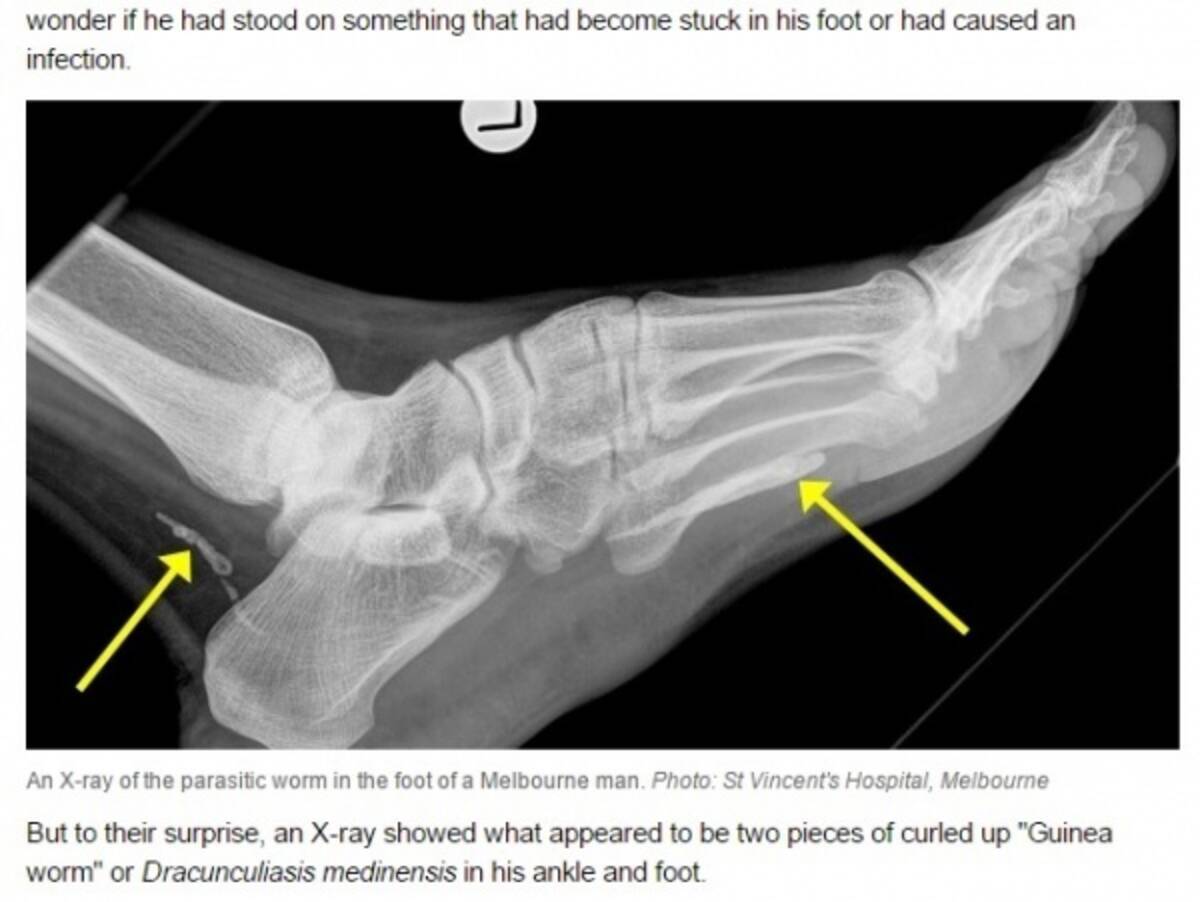

数年後に足首が腫れて感染が発覚 脅威の寄生虫 ギニアワーム 豪 2014年12月14日 エキサイトニュース